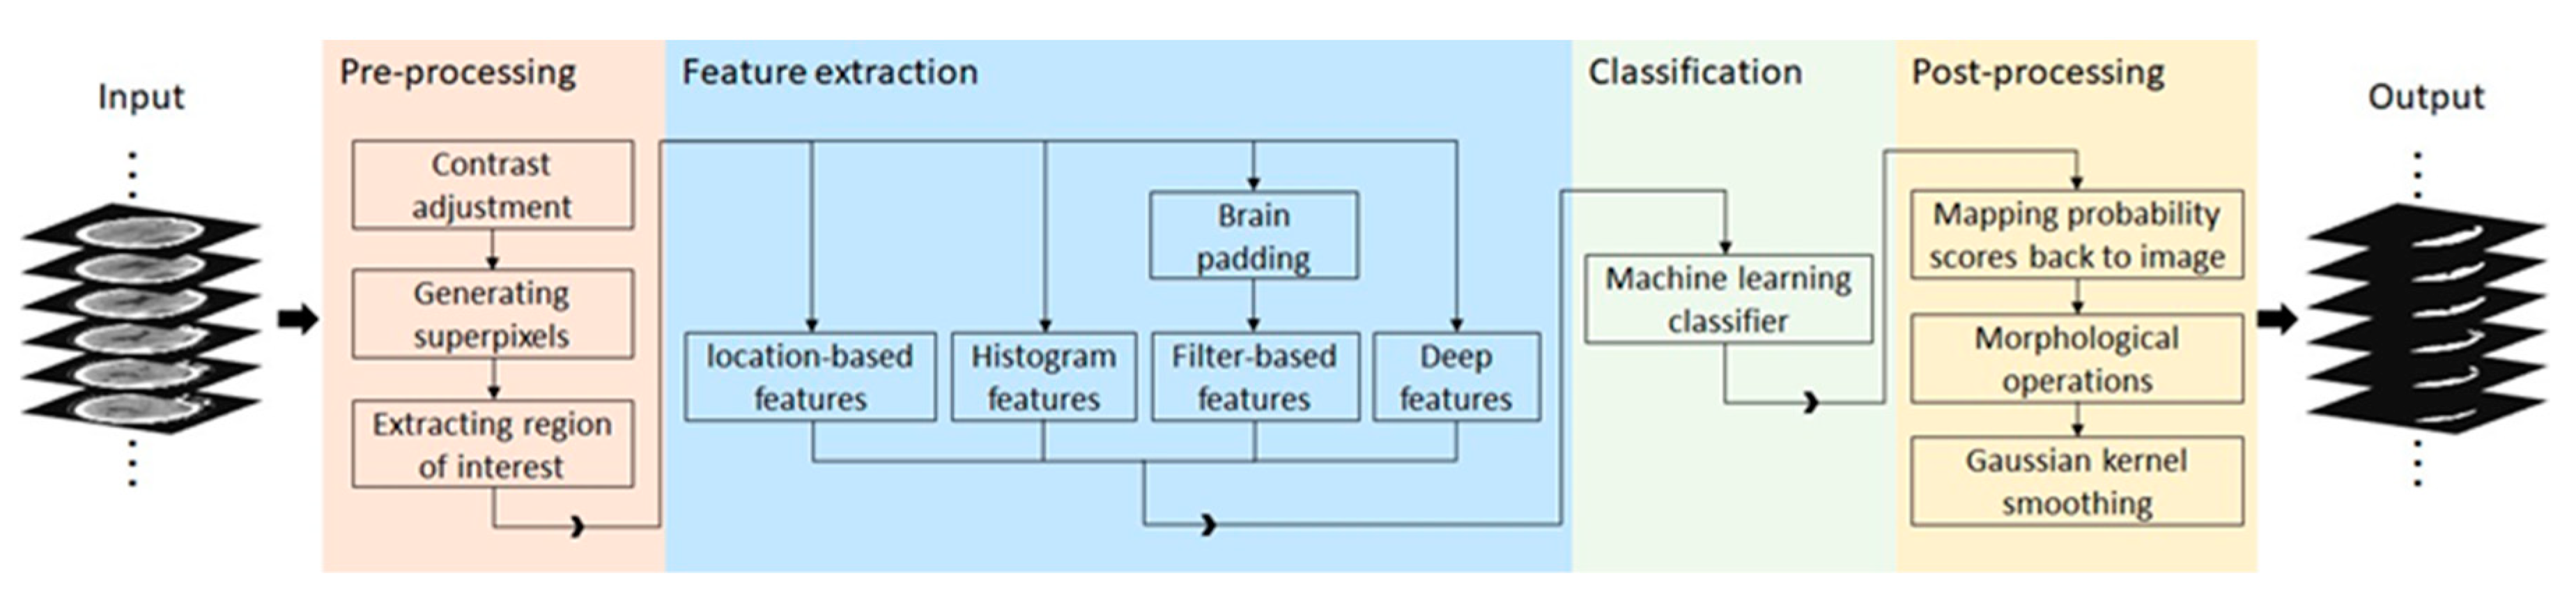

The study design for SDH segmentation and severity assessment are shown in

Figure 1. We first developed a machine learning model using 10 fold cross validation to segment SDH regions. Then, we employed the automatically segmented region to assess the severity of SDH.

3.5. Machine Learning Pipeline

Figure 2 demonstrates a high-level overview of the proposed method. Given a head CT scan, we first performed pre-processing to identify the region of interest (ROI). Next, potential discriminative patterns were extracted from the ROI, followed by using a random forest classifier to identify SDH regions. Finally, in the post-processing step, morphological operations and Gaussian kernel smoothing were used to improve overall segmentation performance.